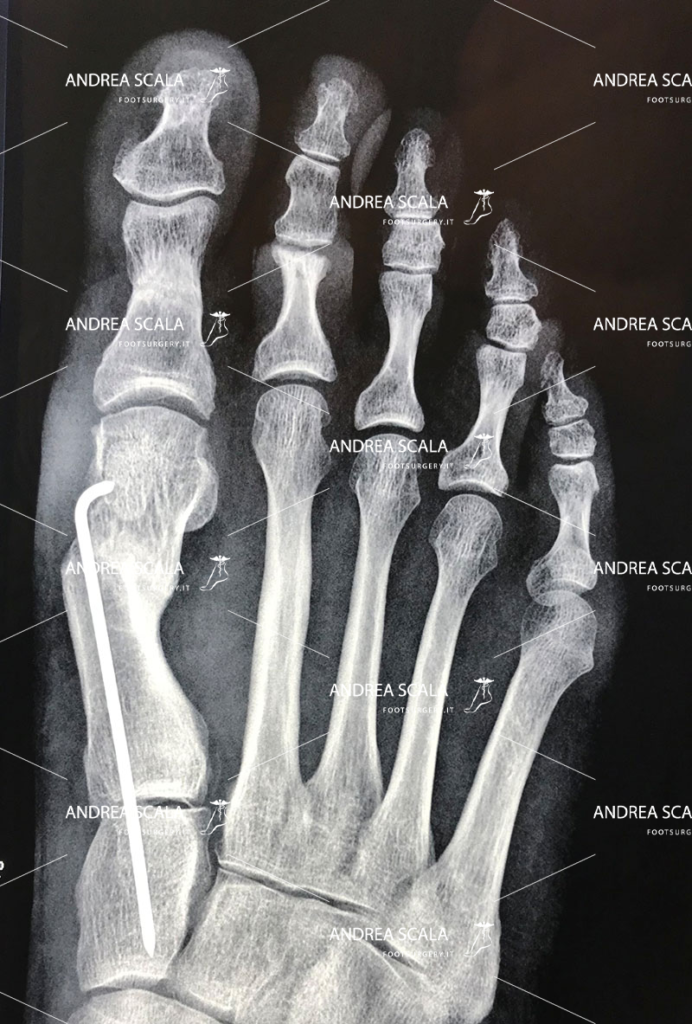

L’operazione dell’alluce eseguita con tecnica mininvasiva (con una minima incisione).

Il dott. Andrea Scala ha messo a punto una tecnica, pubblicata in U.S.A. nel 2013 che supera i problemi che la tecnica percutanea comporta.

Grazie a questa tecnica è possibile sezionare l’osso deformato per riposizionarlo e riallinearlo con le altre dita del piede, il tutto effettuando solo un’incisione di pochi millimetri sulla cute. La minima incisione taglia l’osso con precisione ed evita di tagliare anche tendini, vasi e nervi. Al termine dell’intervento un piccolo chiodo di 1 millimetro aiuta l’osso tagliato a guarire nella posizione corretta e assicura che l’alluce operato non tornerà mai più.

Proprio per questo il paziente dovrà deambulare con delle apposite scarpe, una volta terminato l’intervento. Generalmente il decorso post – operatorio prevede un ciclo di medicazioni ogni 15 giorni. Dopo solo un mese sarà possibile tornare alle proprie attività, e nel caso degli sportivi, dopo 3 mesi sarà già possibile riprendere l’attività agonistica.